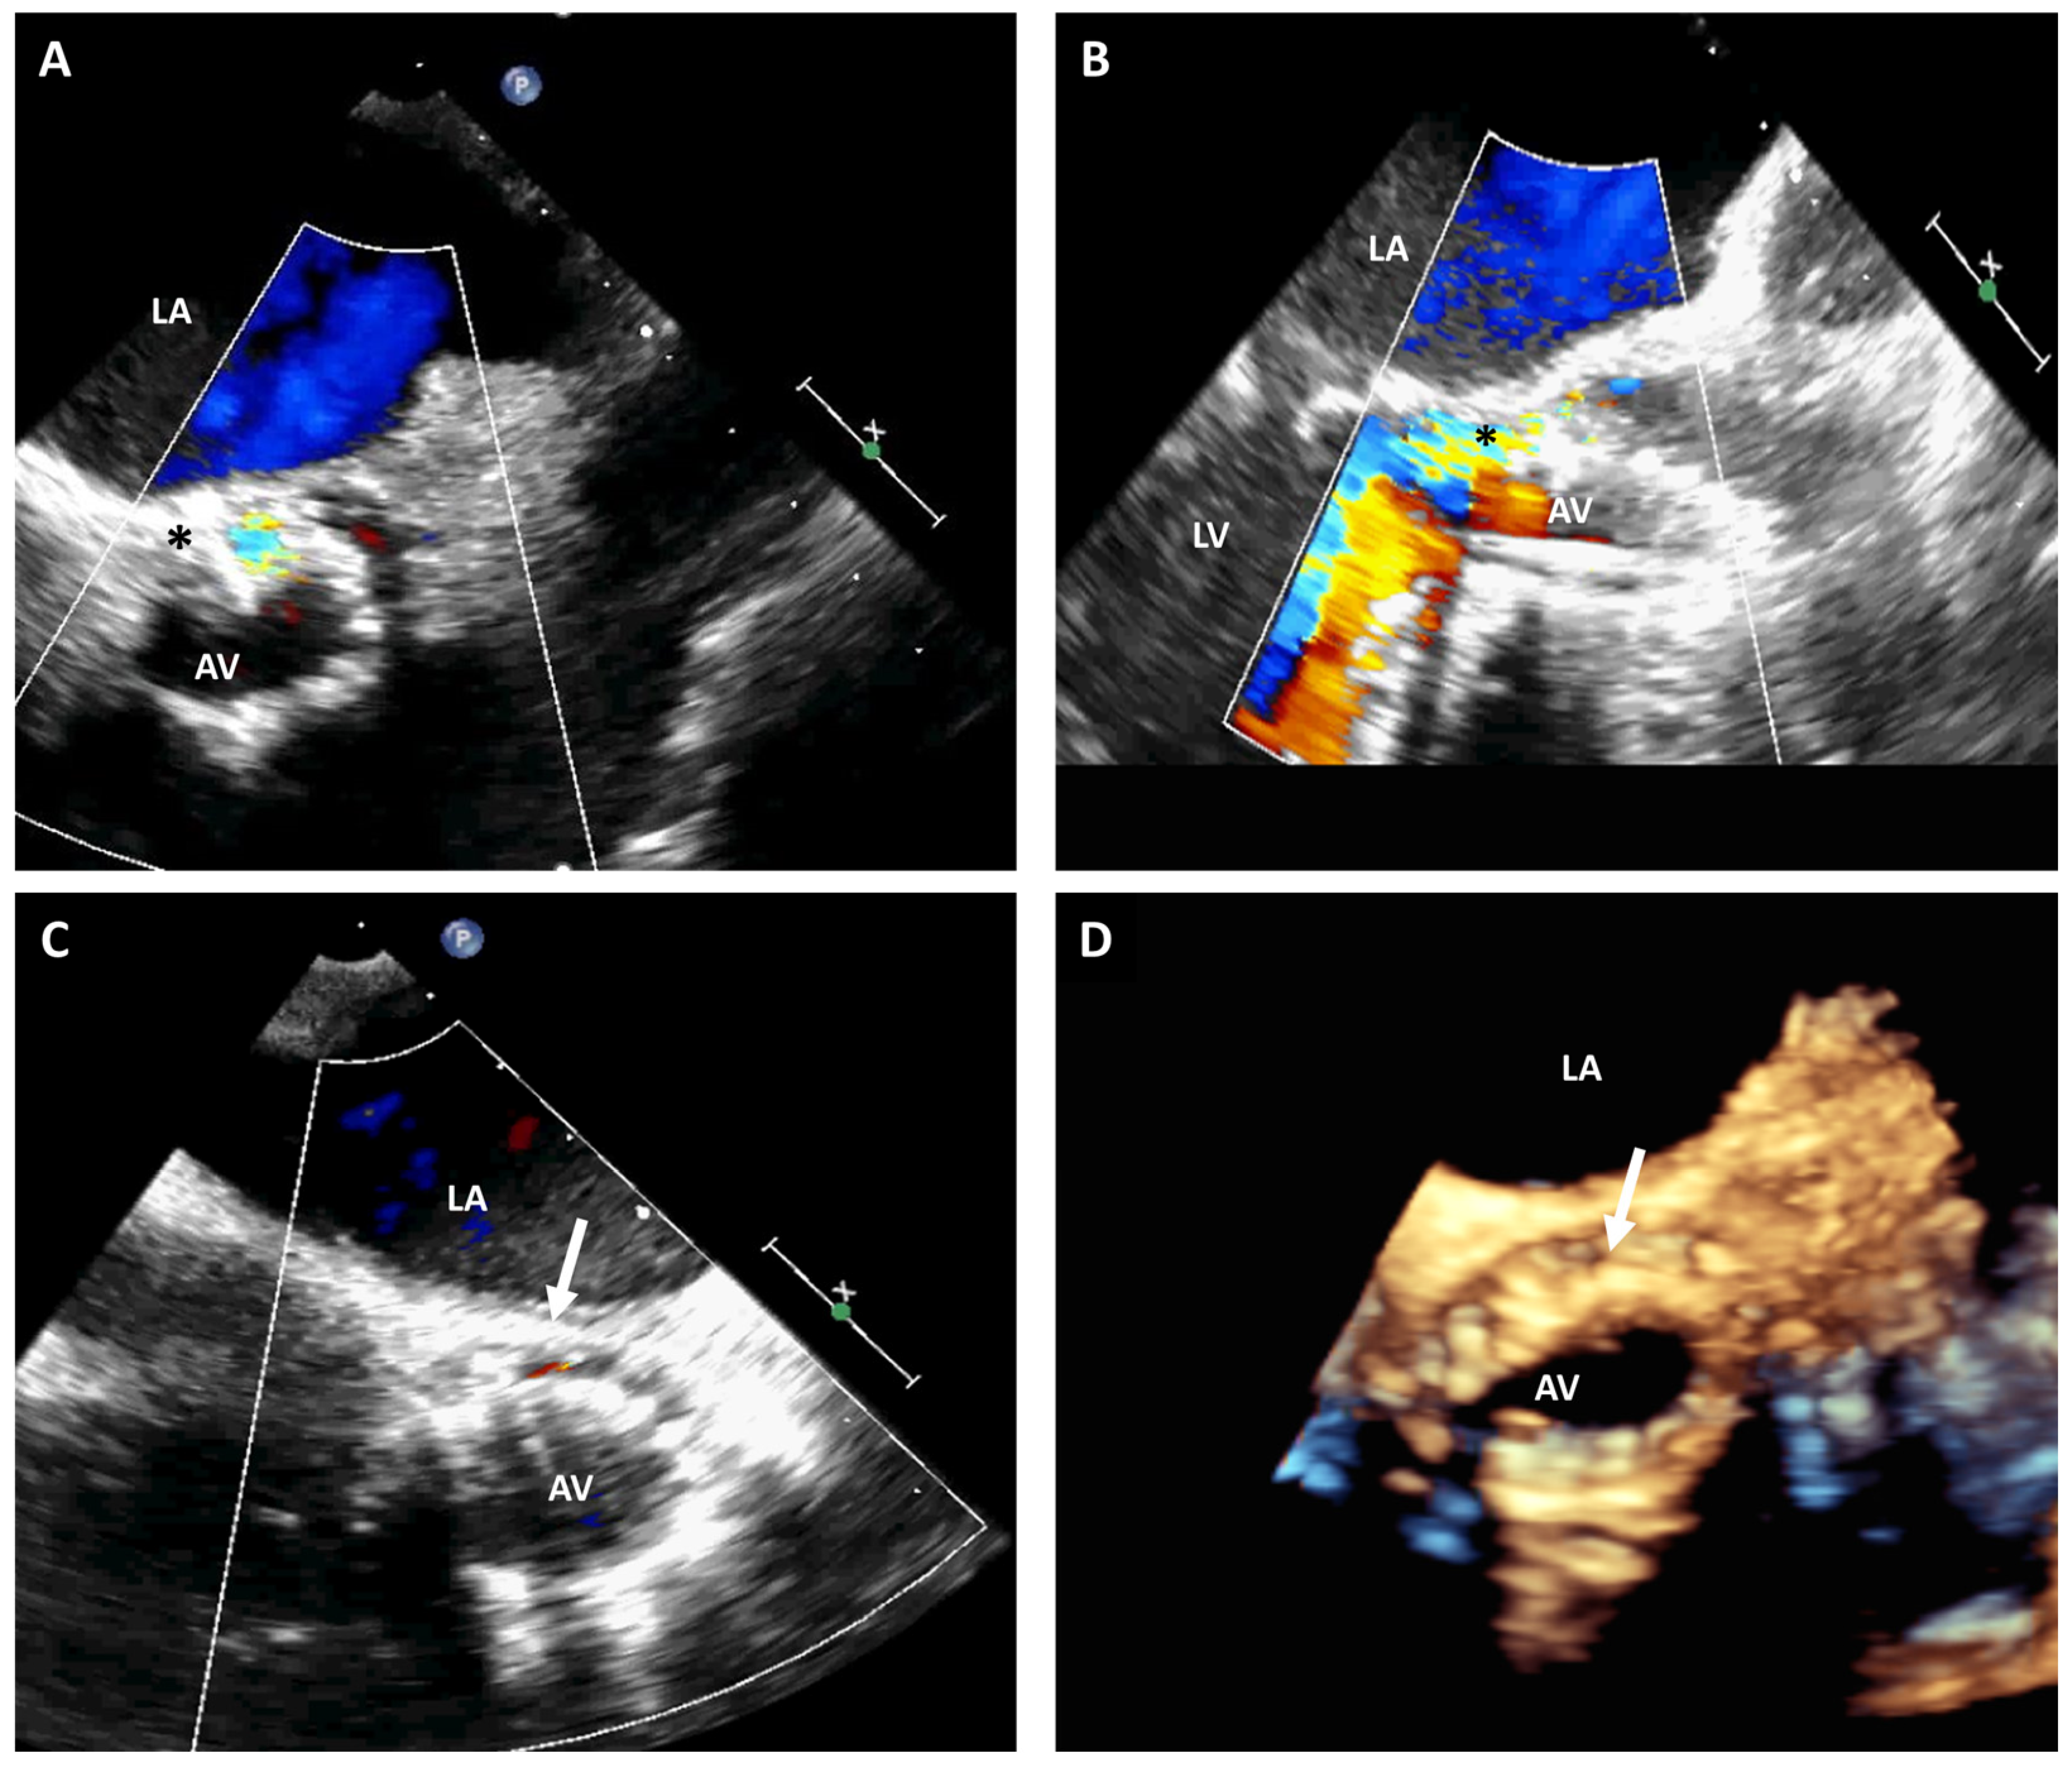

2. Trans-Septal Puncture

3.1. Transcatheter Aortic Valve Replacement